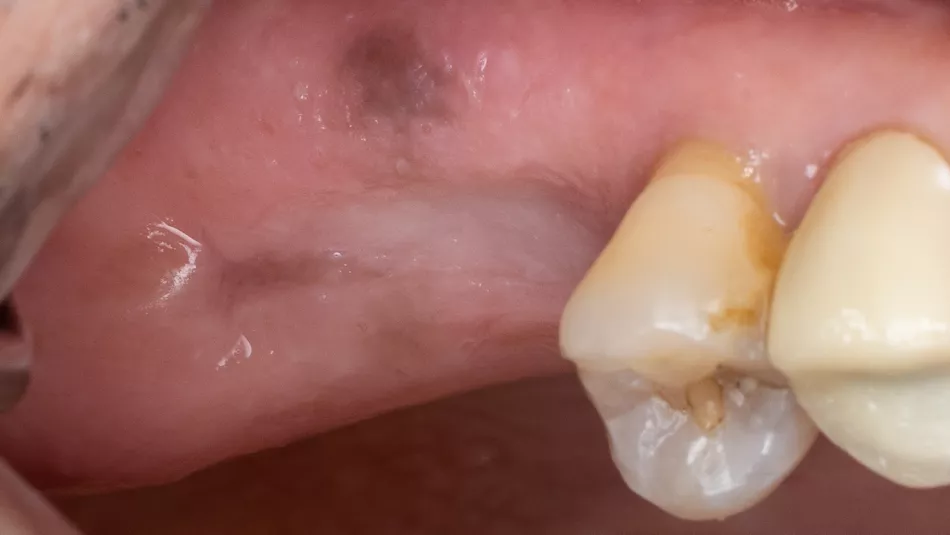

1. Pre-operative clinical view

The occlusal view shows a ridge with a satisfactory width and a thick, healthy periodontal phenotype.